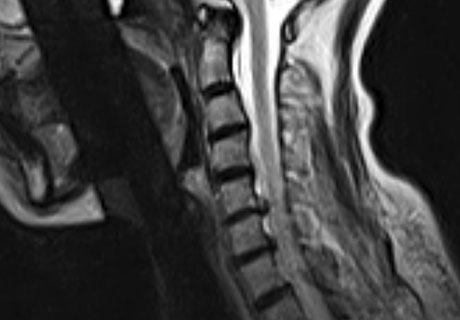

목 디스크는 목의 디스크(경추 디스크)에서 출현하는 질환으로, 경추 디스크 사이의 연골판이 터져 디스크 내부 물질이 경추 신경을 자극해 통증이나 저림증 등의 증상을 유발 해요. 목 디스크는 일상생활에서의 안 좋은 자세나 많은 운동, 부상 등이 이유가 되는 것이 될 수 있기도하고, 시간이 지날수록 발생 확률이 높아져요. 목 디스크의 증상으로는 목 부위의 통증, 팔의 저림, 근육 약화 등이 있으며, 증상이 난폭한 경우 수술 등의 치료가 필요할 수 있어요. 그리하나 대개의 경우 치료 없이도 시간이 지나면 증상이 호전되는 경우가 대부분입니다.

추간판의 수핵이 빠지거나 퇴행성 경추증 및 경추관협착증 등으로 척수가 압박되면 대다수 팔에 힘이 빠지는 것을 느끼게 돼요. 척수가 눌리는 정도이기 때문에 한쪽 팔만 마비될 수 있고요. 하지마는 양팔의 감각이 둔해지고 눈을 감고도 어지럽기 때문에 이러한 목 디스크 증상이 나타나면 무척 위험한 상태가 되기 때문에 빨리 치료가 필요해요.